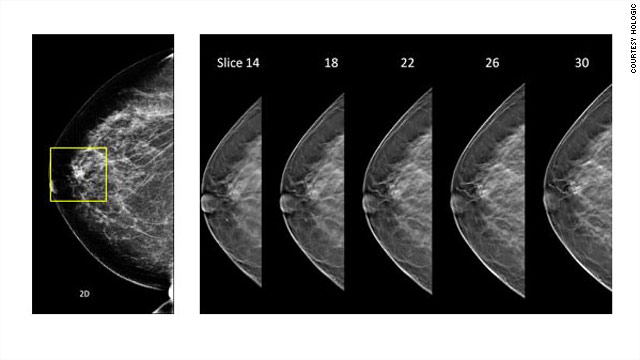

The U.S. Food and Drug Administration on Friday approved the first 3-D mammography imaging system.

In this type of screening,  images in many thin slices are combined or "stacked" to create a 3-D vision of the breast. The test  is similar to routine 2-D mammography with some compression and some additional radiation that is within the FDA guidelines, Destounis explained.